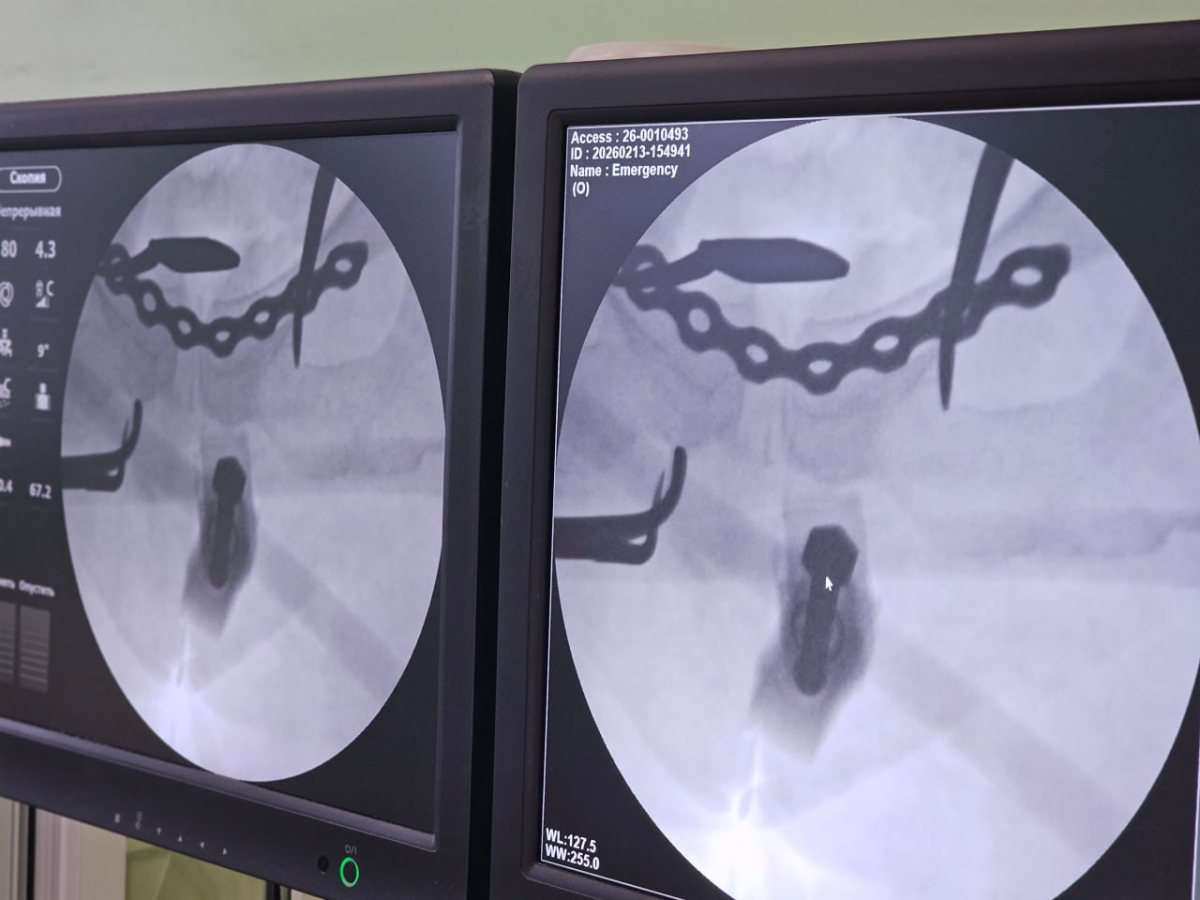

41-летняя женщина в январе упала с «ватрушки» на большой скорости и переломала себе таз. Медики из БСМП №1, куда попала пациентка, поставили крайне тяжёлый диагноз: перелом боковых масс крестца с двух сторон и разрыв лонного сочленения (вертикального соединения верхних ветвей лобковых костей).

Местной жительнице помощь оказывали в два этапа. Как только она поступила в больницу, ей провели закрытую репозицию перелома костей таза (процедуру, направленную на восстановление нормального анатомического положения костных отломков) со стабилизацией аппаратом внешней фиксации. Вся операция заняла всего 20 минут.

На втором этапе – после тщательного обследования и предоперационного планирования – пациентке окончательно зафиксировали переломы специализированными металлоконструкциями – винтами и титановой пластиной.